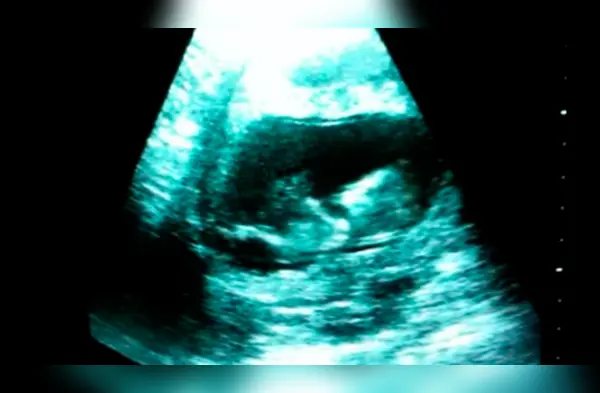

El video del que te mencionamos, fue publicado por Sherine Gayle-Slate, la madre de la niña que verás a continuación. En el clip se muestra el ultrasonido en el que la bebé de Sherine se desliza por el útero en un impulso que la lleva hacia atrás y nuevamente se resbala por el vientre.

“En una ultrasonografía improvisada, vimos a nuestra hija oscilando con el cordón umbilical. Parecía que estaba haciendo gimnasia”, escribió la madre en la descripción del video. El clip se ha vuelto un viral en todo el mundo obteniendo más de 5.739.523 visualizaciones y 2.5 mil “me gustas”.